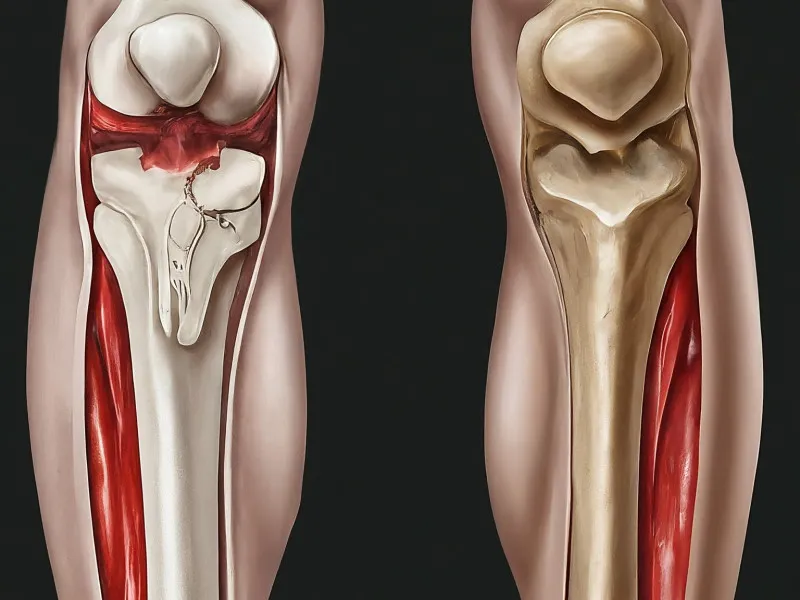

Microfracture involves creating small holes in the joint surface to stimulate a healing response. Initially, this technique showed promising results in athletes with joint injuries. However, the results often deteriorate over time. The underlying issue is that the body struggles to balance between durable healing and repeated injury from weight-bearing activities, leading to the breakdown of repair tissue over a few years.

The articular cartilage covering joint surfaces is smooth and essential for joint movement. When injured, the smooth surface becomes rough, leading to pain and mobility issues. Unfortunately, the cartilage’s capacity to heal is limited. The repair tissue formed is usually not the same as normal cartilage, leading to pain recurrence. Over time, the absence of adequate healing exacerbates the initial damage, resulting in post-traumatic arthritis and deformation of the underlying bone.

Microfracture’s long-term outcomes are variable. A study revealed that while scores like IKDC, Lysholm, and Tegner increased significantly at 2 years post-treatment, they gradually deteriorated in the long term. Additionally, the risk of osteoarthritis progression was higher in older patients with larger or multiple lesions. Another concern is the formation of cysts in the bone due to unhealed bone cavities, causing pain and bone deformity.